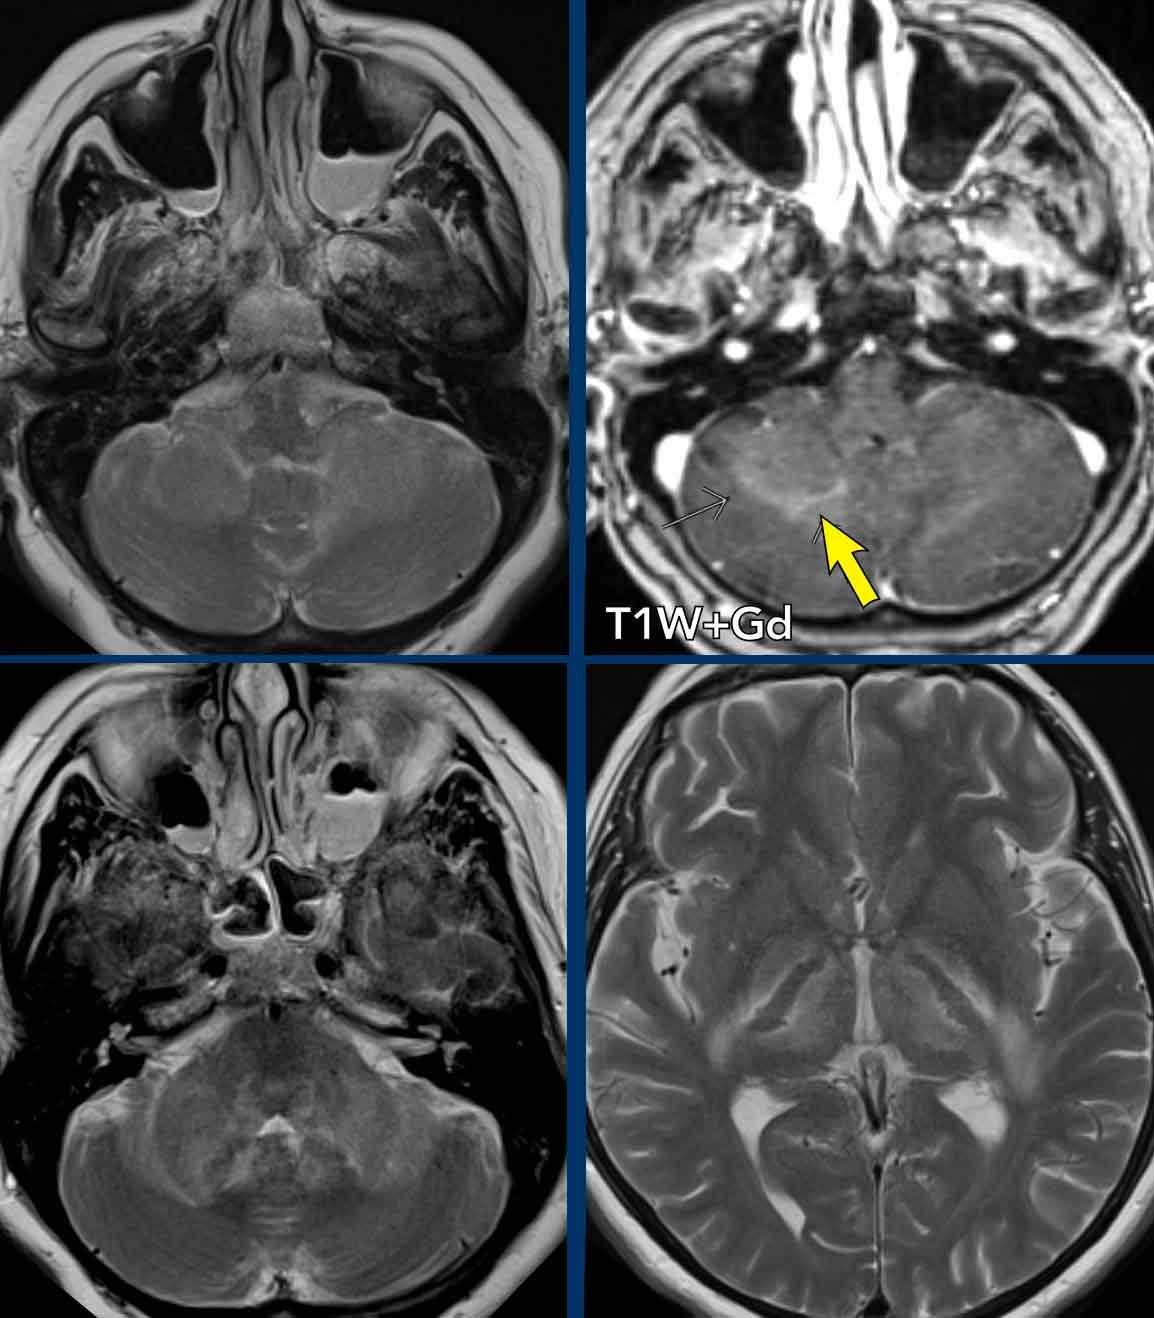

Những hình ảnh này của một bệnh nhân đã được điều trị bằng kháng sinh cho chứng ho kéo dài trong ba tuần.

Bệnh nhân hiện đến phòng cấp cứu với triệu chứng buồn nôn đột ngột, nôn mửa, chóng mặt và song thị (nhìn đôi).

Khi thăm khám, bệnh nhân có hội chứng Horner hai bên.

Hình ảnh

Đây là giao thức chụp giới hạn (T2W và DWI) chỉ nhằm mục đích tìm kiếm các dấu hiệu thiếu máu cục bộ.

Không có hạn chế khuếch tán (không hiển thị) và thiếu máu cục bộ cấp tính đã được loại trừ.

Có một tổn thương lớn với hiệu ứng khối chèn ép hạn chế ở cuống tiểu não trái và có mức khí-dịch hai bên trong các xoang hàm.

Continue with the follow up scan two days later…

Đầu tiên hãy xem bốn hình ảnh.

Những phát hiện là gì và chẩn đoán phân biệt của bạn là gì?

Images

- Tổn thương ở cả hai cuống tiểu não, cho thấy sự tiến triển rất nhanh chỉ trong vòng hai ngày.

- Peripheral enhancement of the lesion on the right (arrow).

- Lesions in both thalami

- Tổn thương ở bao ngoài nhiều hơn ở bên trái (hình dưới bên phải).

- Diffusion was still normal (not shown).

Thảo luận

Với kiểu tiến triển nhanh của bệnh này, có thể loại trừ khối u.

Chẩn đoán phân biệt tập trung vào bệnh mất myelin và viêm não sau (rhombencephalitis).

Viêm não sau là một bệnh viêm ảnh hưởng đến thân não và tiểu não với nhiều nguyên nhân khác nhau, bao gồm nhiễm trùng, bệnh tự miễn và hội chứng cận u.

Continue…

Kết luận

Cuối cùng, chẩn đoán có khả năng nhất là viêm não hình thoi do viêm.

Bệnh nhân hồi phục chậm.